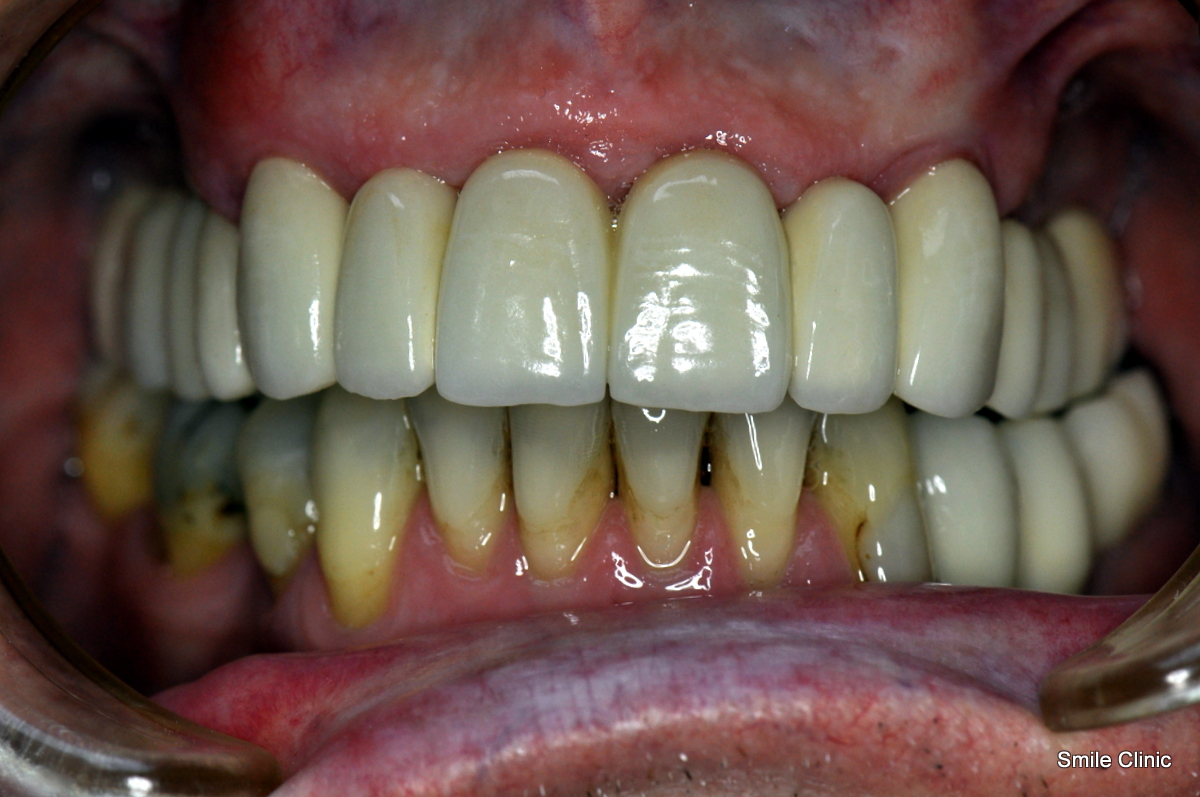

He had been wearing false upper teeth for some time, and decided to finally get rid of it by opting for the “all on 6” dental implant procedure giving him 12 new, fixed teeth for his upper jaw on 6 dental implants, as well as a crown tooth bridge of 4 teeth for the bottom jaw towards the back for added eating strength.

As you can see from the photographs, David opted for a natural look, complementing his original teeth – with an improved smile & confidence.